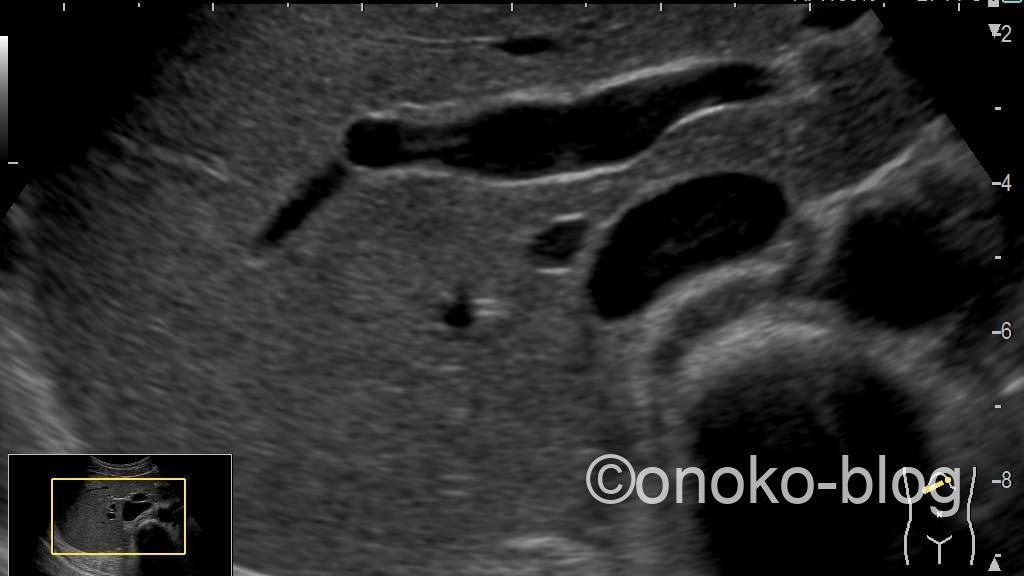

続いてRead Zoomです。

じゅうぶんキレイな画像ですが、Write Zoomに比べると少し柔らかさを感じます。